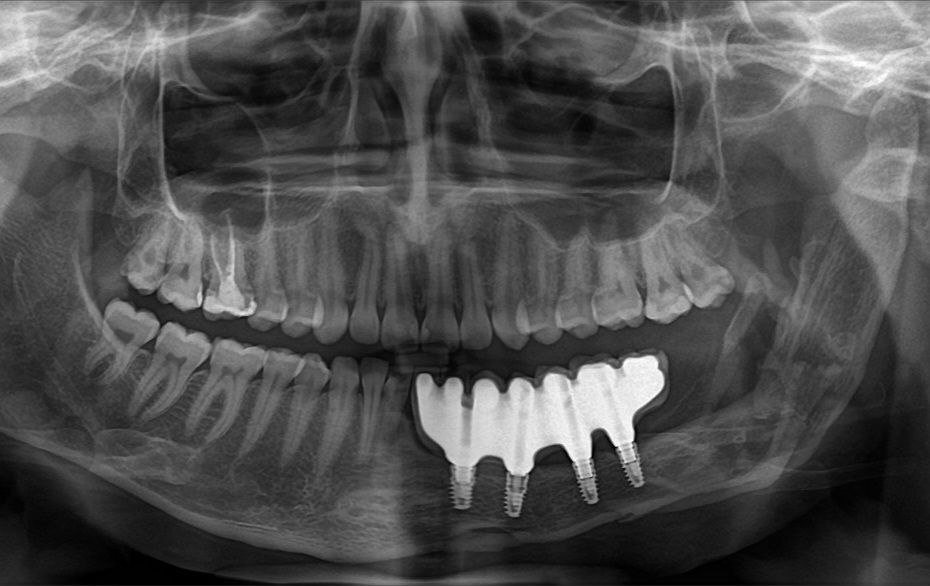

Мы показывали вам протезирование после травмы. Показываем протезирование после онкологии и удаления челюстей. Протезирование после удаления фрагмента челюсти — это огромная сложность. Заключается в том, что постоянное протезирование на имплантате возможно при условии, что мы можем установить в трансплантированную кость импланты. Что достаточно её объема. Помимо этого, ещё высок риск отторжения самой кости или имплантатов. Что касается создания прикуса, никакой протез не будет соответствовать по форме удаленной нижней челюсти на 100%. То есть у нас получается "какая-то" челюсть. Благодаря специальной предоперационной подготовке и послеоперационной реабилитации — не сместившаяся в сторону дефекта и сохранившая центральную линию. Вот в таких сложных условиях, нам удалось создать прекрасную красивую улыбку и функциональный прикус (не смотря на небольшой перекрест, зубы не задевают и не травмируют друг друга и активно участвуют в пережевывании пищи) нашей пациентке.

Протезирование после удаления фрагмента челюсти — это огромная сложность. Заключается в том, что постоянное протезирование на имплантате возможно при условии, что мы можем установить в трансплантированную кость импланты. Что достаточно её объема. Помимо этого, ещё высок риск отторжения самой кости или имплантатов.

Что касается создания прикуса, никакой протез не будет соответствовать по форме удаленной нижней челюсти на 100%. То есть у нас получается "какая-то" челюсть. Благодаря специальной предоперационной подготовке и послеоперационной реабилитации — не сместившаяся в сторону дефекта и сохранившая центральную линию.

Вот в таких сложных условиях, нам удалось создать прекрасную красивую улыбку и функциональный прикус (не смотря на небольшой перекрест, зубы не задевают и не травмируют друг друга и активно участвуют в пережевывании пищи) нашей пациентке.